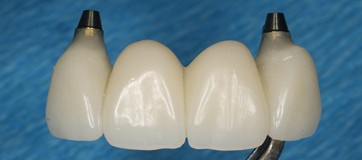

Since temp shells were already fabricated, we were ready to pick up our temporary prosthesis using non-engaging temporary abutments.

When picking up a multiple unit bridge on temporary abutments, make sure to never use flowable due to possible shrinkage of the material and only use self-curing no-shrinkage resin based material (Integrity).

Once the temporary is picked up and emergence profile is customized to have an adequate regenerative space and properly placed Critical contour (0.5 short of the final gingival margin) we are ready to deliver the prosthesis.